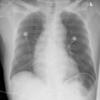

Ao Diss 3

Date: 02/26/2006

Views: 2885